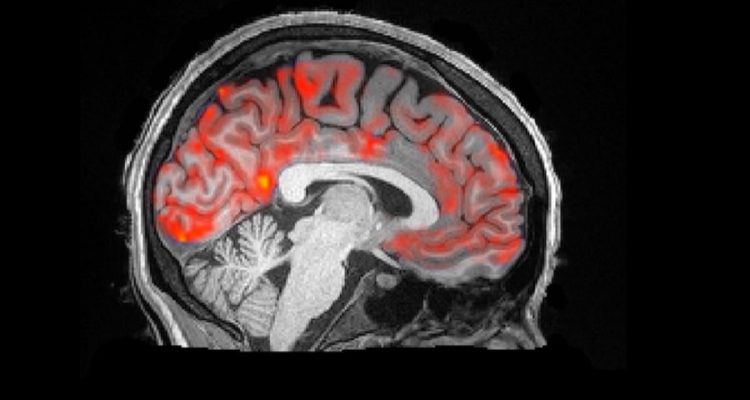

Previous studies have suggested that LCS is important for the elimination of brain toxins, but so far neuroscientists have not known or been able to observe this pulsating action. Combined with slow-wave brain activity (which partly serves to fix our memories) and the decreased blood flow that occurs during sleep, these CSF waves seem to eliminate unnecessary protein.![]() |

| Graph showing a rise in the frequency of CSF waves during sleep (blue zone) compared to the waking state (pink zone). The data was obtained by fMRI. Credits: Nina E. Fultz et al. 2019 |